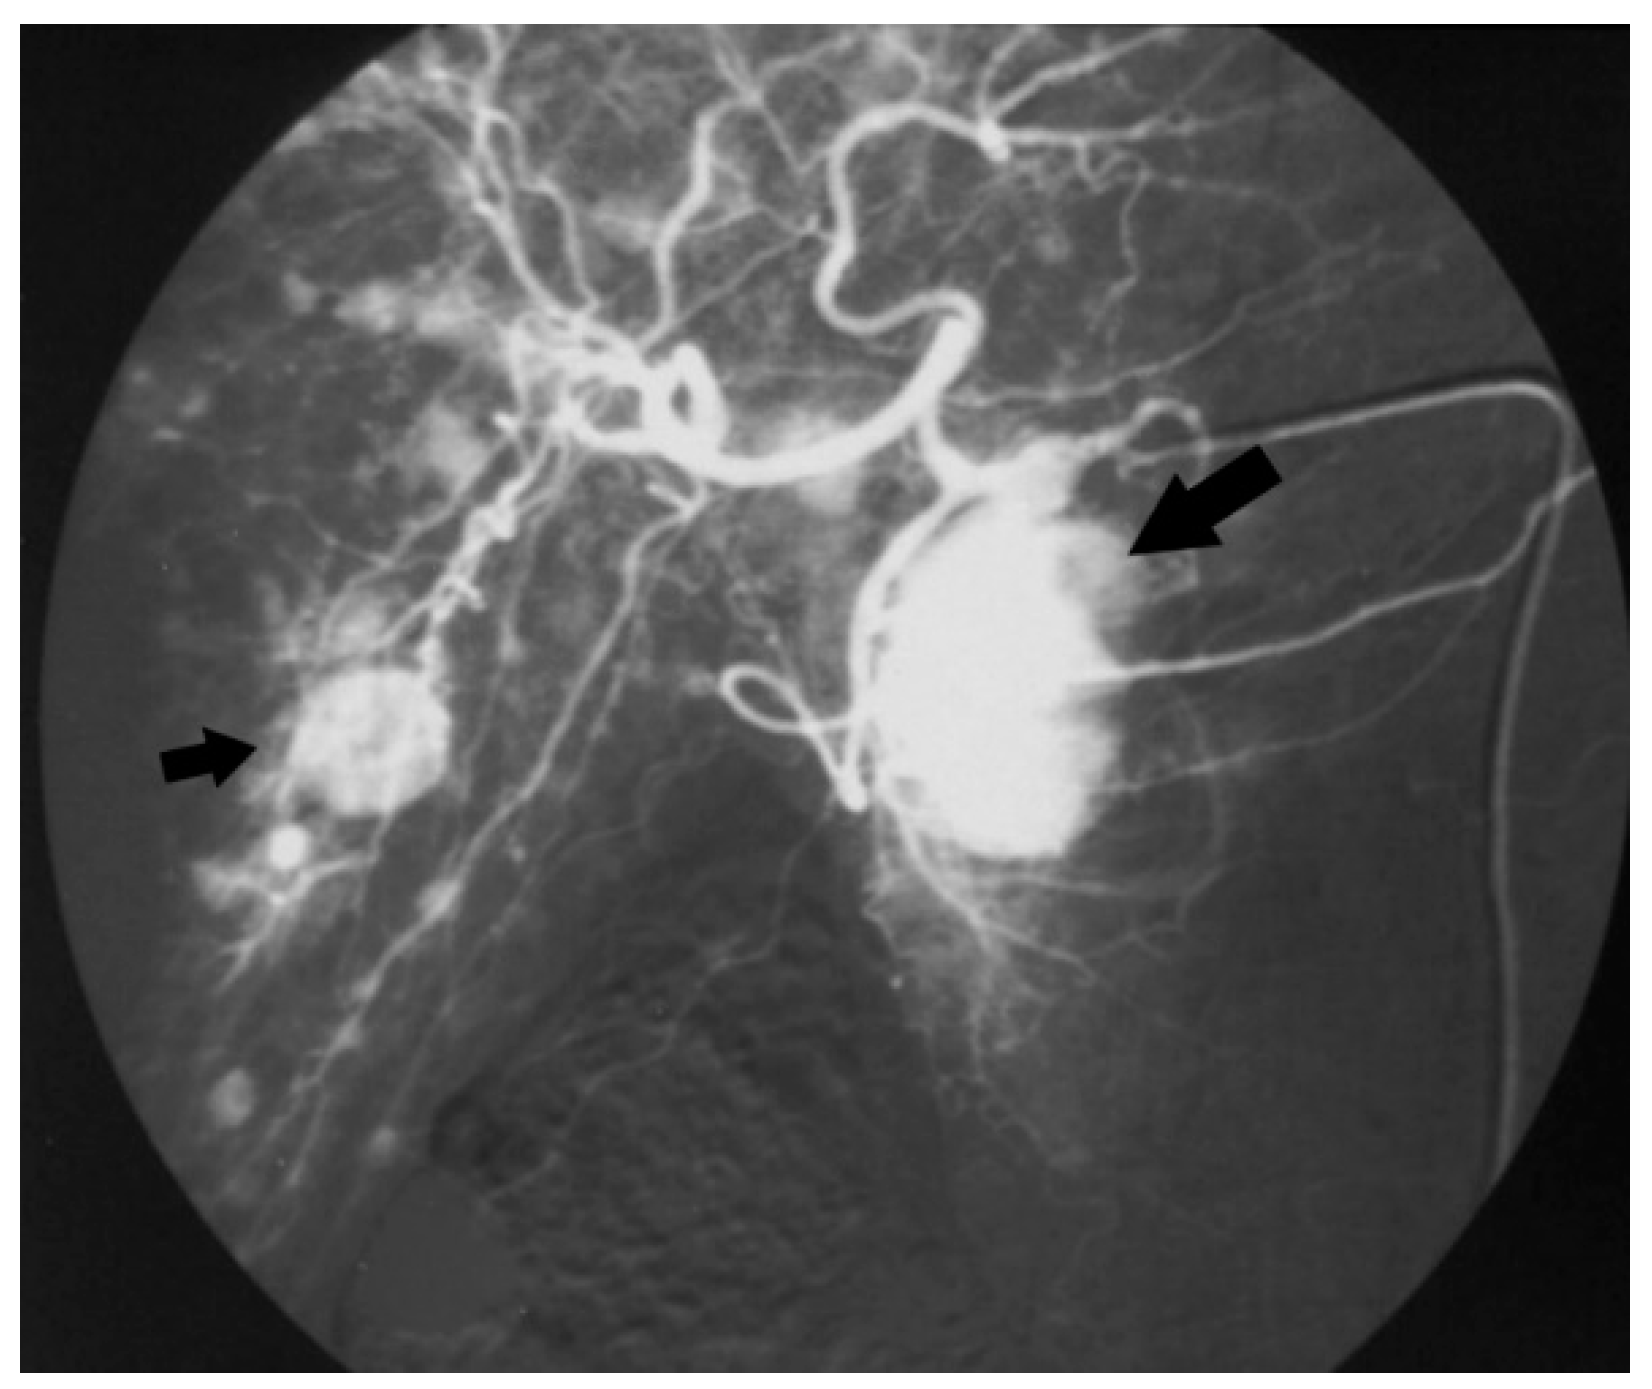

| 1 | Head 4.0 | Bilobar liver | Liver | T2 Nx M1 IV | NET n.a. | 5-HT 20–20–30% Grimelius | Insulin, Gastrin, PP | SS-A, CT a | 158 | DOD |

| 2 | Tail 2.5 | Bilobar liver | Liver | T2 Nx M1 IV | NET n.a. | CgA | n.a. | TACE | 12 | DOD |

| 3 | Body 4.0 | Bilobar liver, mediastinal LN | Liver | T2 N1 M1 IV | NET n.a. | CgA, Grimelius | n.a. | CT b | 29 | DOD |

| 4 | Tail 6.0 | Bilobar liver | Abdominal LN | T3 N1 M1 IV | NET 3.4% | CgA, Syn, NSE | 5-HT, Insulin, Gastrin, Glucagon, SS, PP, Calcitonin | SS-A, CT b, TAE, PRRT | 96 | DOD |

| 5 | Body 10.0 | Bilobar liver, cervical LN | Cervical LN | T4 N1 M1 IV | NEC n.a. | n.a. | n.a. | SS-A, CT c | 16 | DOD |

| 6 | Body 4.0 | Bilobar liver | Liver | T2 N1 M1 IV | NET 16% | CgA, Syn | n.a. | Biliary stent SS-A, CT d Liver MW Everolimus | 117 | AWD |

| 7 | Body 3.6 | Bilobar liver | Liver | T2 Nx M1 IV | NET 70% | 5-HT, CgA, Syn, Calcitonin | NSE, Insulin, Gastrin, Glucagon, SS, PP, VIP | CT e | 5 | DOD |